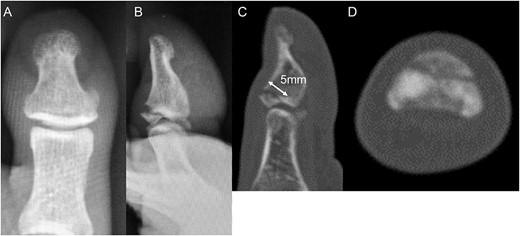

A 54-year-old man injured his right great toe while walking and wearing sandals. He complained of tenderness, swelling, and pain during motion. He could bear weight but could not actively extend the interphalangeal (IP) joint of the hallux. He was referred to our outpatient clinic 3 days after the injury. Physical examination revealed swelling, tenderness, and motion pain, and the patient could not extend the IP joint of the hallux. Plain lateral radiography and computed tomography revealed a displaced avulsion fracture of the dorsal base of the distal phalanx (Fig. 1). Surgery was performed under general anesthesia after informed consent was obtained on posttraumatic day 11. A Y-shaped incision was made at the center of the dorsal IP joint, and the displaced bony fragment was attached to the extensor hallucis longus (EHL). The IP joint was temporarily fixed with a 1.6 mm Kirschner wire, and the fragment was repositioned and fixed with two 1.5 mm cortical screws (APTUS® Hand, Medartis, Basel, Switzerland). A 4-0 FiberWire® (Arthrex, Naples, FL, USA) was fastened as an augmentation proximally to the EHL tendon and distally to the periosteum of the distal phalanx in a figure eight (Fig. 2). Postoperatively, the ankle was externally fixed in dorsiflexion from the leg to the toe, and heel loading was permitted. A total of 4 weeks after surgery, the Kirschner wire was removed to allow active motion of the IP joint of the hallux, and weight bearing was allowed on the hallux 5 weeks postoperatively. Plain radiographs taken 3 months after surgery confirmed bone healing (Fig. 3). A total of 20 months postoperatively, the patient acquired normal function, and the range of motion of the affected IP joint ranged from −3° to 30°, with no difference from the unaffected side (Fig. 4). Skin necrosis or nail deformities were not observed.

Operative findings (A) showed a bone fragment attached to the EHL (arrowhead) and (B) fixed with two screws (arrows). (C) Suture augmentation technique with FiberWire® (dotted line) proximally sutured to the EHL and distally sutured to the periosteum.